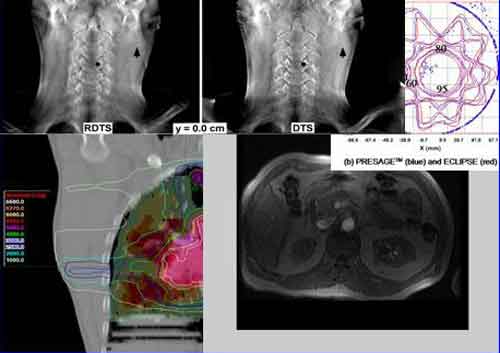

La chirurgia radioguidata e’ una tecnica che mira all’identificazione di residui tumorali per permettere una completa resezione in sede operatoria. Si inietta una sostanza radioattiva (un radiofarmaco) che si lega preferenzialmente alle cellule tumorali. Si attende che il farmaco sia metabolizzato e poi, durante l’operazione per l’asporto del tumore, si usa un dispositivo (sonda) in grado di rivelare la radiazione per verificare tessuti su cui si ha il dubbio se siano tumorali o meno. Alla fine della resezione, sempre durante l’operazione, si puo usare la stessa sonda per verificare se siano rimasti residui. Le tecniche di chirurgia radioguidata adottate oggi fanno tutte uso di radiofarmaci che emettono raggi gamma. Questi ultimi attraversano grossi spessori di materiale e sono pertanto utilizzati comunemente in diagnostica medica, e sono dunque un naturale punto di partenza per questa diagnostica. Il loro potere penetrante pero’ comporta che, se c’e’ un organo fortemente captante in prossimita’ del tumore, esso emette un segnale che oscura qualunque segnale proveniente dai residui tumorali.

Inoltre, il personale medico viene investito da una significativa dose di radiazione a meno di tenere le attivita’ del radiofarmaco molto basse. Queste limitazioni rendono la chirurgia radioguidata non applicabile a tumori quali quelli cerebrali (vista l’alta captazione del cervello sano), dell’addome (in prossimita’ di reni, vescica, fegato, per esempio) e pediatrici (dove tutte le dimensioni sono ridotte). “Per superare queste limitazioni – ha spiegato Riccardo Faccini, professore all’Universita’ La Sapienza associato all’Infn – il nostro gruppo di ricerca propone un cambio di paradigma, cioei’ utilizzare radiofarmaci che emettano radiazione ((?-)), invece che gamma: gli elettroni infatti hanno una capacita’ penetrante ridotta rispetto ai fotoni”. Il vantaggio di questa innovazione e’ che la scarsa penetrazione degli elettroni nei tessuti evita il problema della contaminazione da parte di organi sani captanti, e inoltre limita significativamente la radioattivitai’ assorbita dal personale medico.